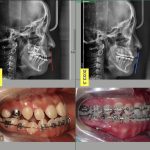

Unday bo'lsa sizga yuqori sifatli Implant xizmatini taklif qilamiz nima uchun ayna biz deysizmi? 10yillik tajribaga va butun Korea bo'ylab TOP5 talikga kiruvchi do'ktorlar sizga xizmat qiladi

Yuqori tajriba baribir o'z foydasini ko'rsatmay qolmaydi shunday ekan siz xoxlagan natijaga erishish uchun sizga albatta yuqori tajribali doktorlar yordami kerak boladi shunay ekan biz shu yerdamiz!